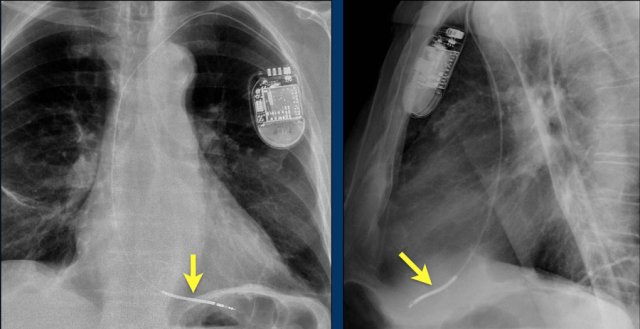

Here a patient with a normally placed ICD on the left image.

Months later there was malfunction due to ICD box and lead rotation (yellow arrow) and retraction (white arrow).

Here another patient with the Twiddler's syndrome.

Notice curling of the lead near the pacemaker and at the tip in the right ventricle (arrows).